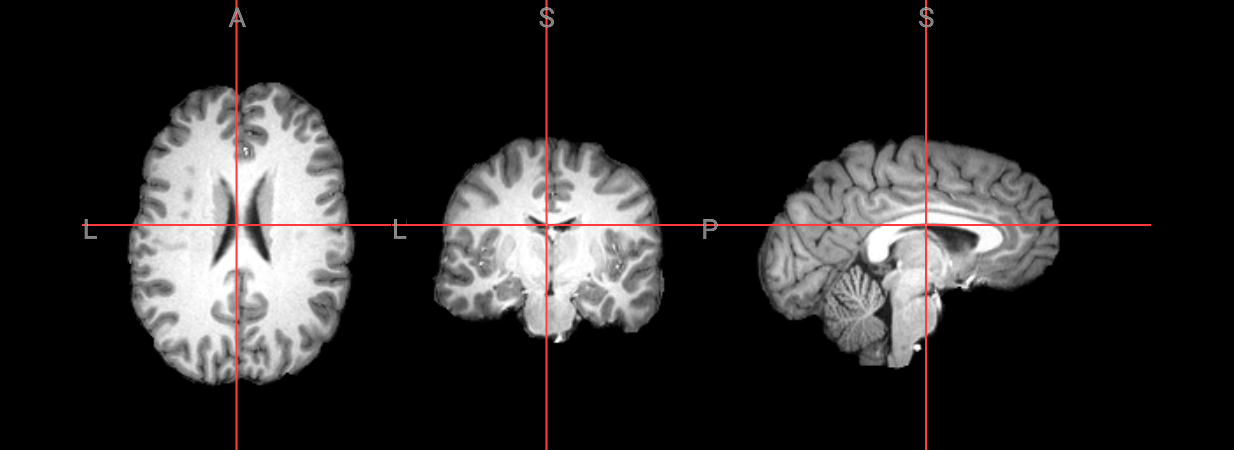

Since fMRI studies focus on brain tissue, our first step is to remove the skull and non-brain areas from the image.

1. ANTs#

First, we will perform brain extraction with this ANTs commands: